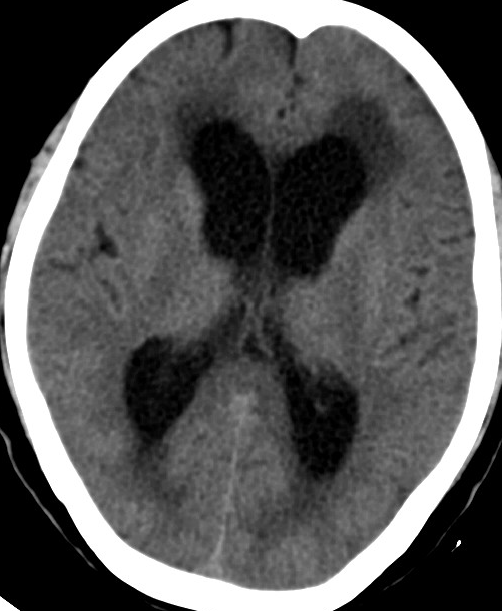

2013-8-2 CT

腰穿脑压240

2013-8-8 CT

2013-8-12 CT

2014-2-10 CT

2014-3-17 CT

2014-10-17 CT